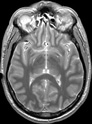

Visible Human male: Sectio transversalis 1099

NMR

Pd T1 T2